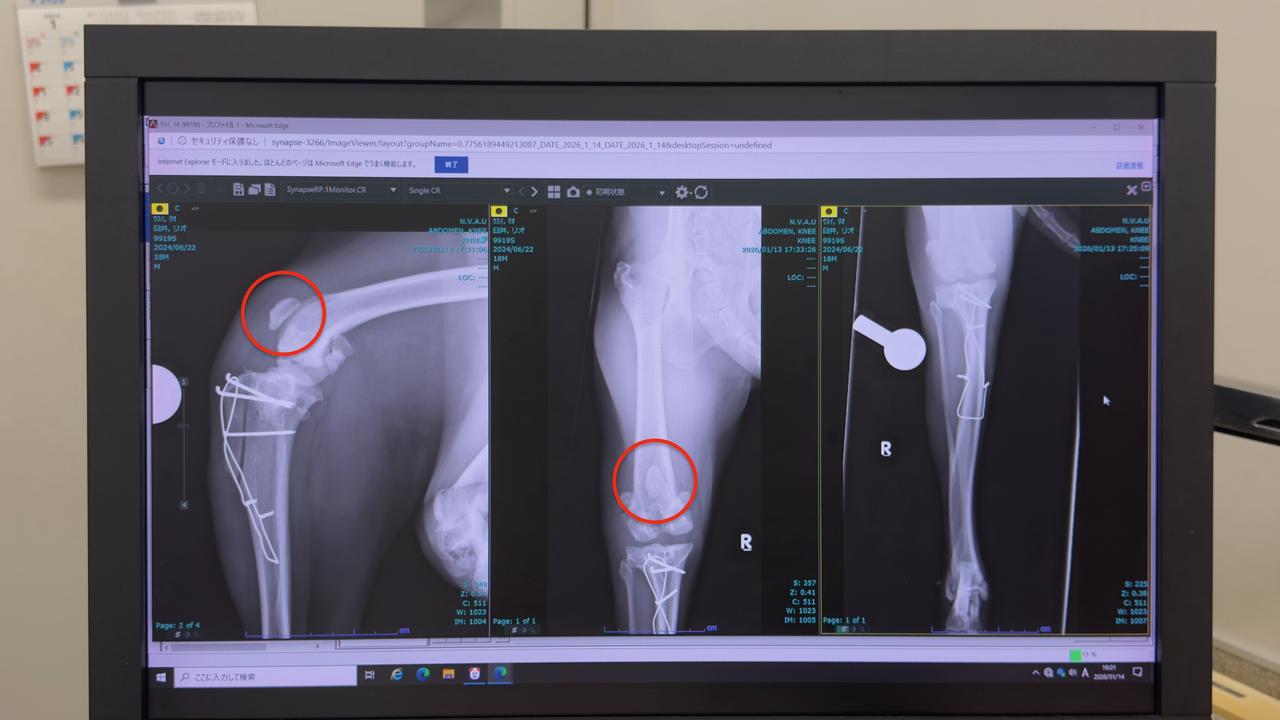

リオの右脚膝蓋骨脱臼手術について

かねてからのご報告通り手術は無事成功しました。現在、自宅で療養中です。

嬉しいことに、想定より軽度だったため、予定していた大腿骨骨切り術と前十字靭帯断裂に対するTPLOは必要ありませんでした。

レントゲンを見ると、内包脱臼していた膝蓋骨がちゃんと正しい位置に整復されています